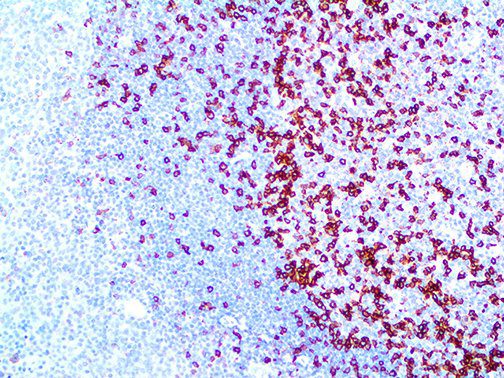

The first cytokines released are interleukin 1β (IL-1β) and tumor necrosis factor-α (TNF-α), which attract a variety of circulating white blood cells (WBCs) to the infection site, including neutrophils, monocytes, macrophages, and natural killer (NK) cells. This response, along with the antipathogenic chemicals released by these cells (i.e., complement), comprise the innate immune response. These cells directly attack the invading pathogen and also release additional cytokines, chief among them interleukin-1 and 6 (IL-6). IL-6 is essential for invoking the adaptive immune response, which calls T-cells, B-cells, and T helper (Th) cells to the infection site. IL-6 also stimulates further recruitment, proliferation and activation of macrophages.

It is the ICU physician who is most likely to witness one of the deadliest manifestations of the abnormal immunological response, the cytokine storm syndrome (CSS). This response is also referred to by some as the cytokine release syndrome (CRS). CSS is characterized by continuous activation and expansion of macrophage and lymphocyte populations, which secrete large amounts of cytokines, causing the cytokine storm. This massive cytokine release is akin to hemophagocytic lymphohistiocytosis (HLH) disease, a syndrome characterized by initial unchecked and persistent activation of cytotoxic T lymphocytes and NK cells.